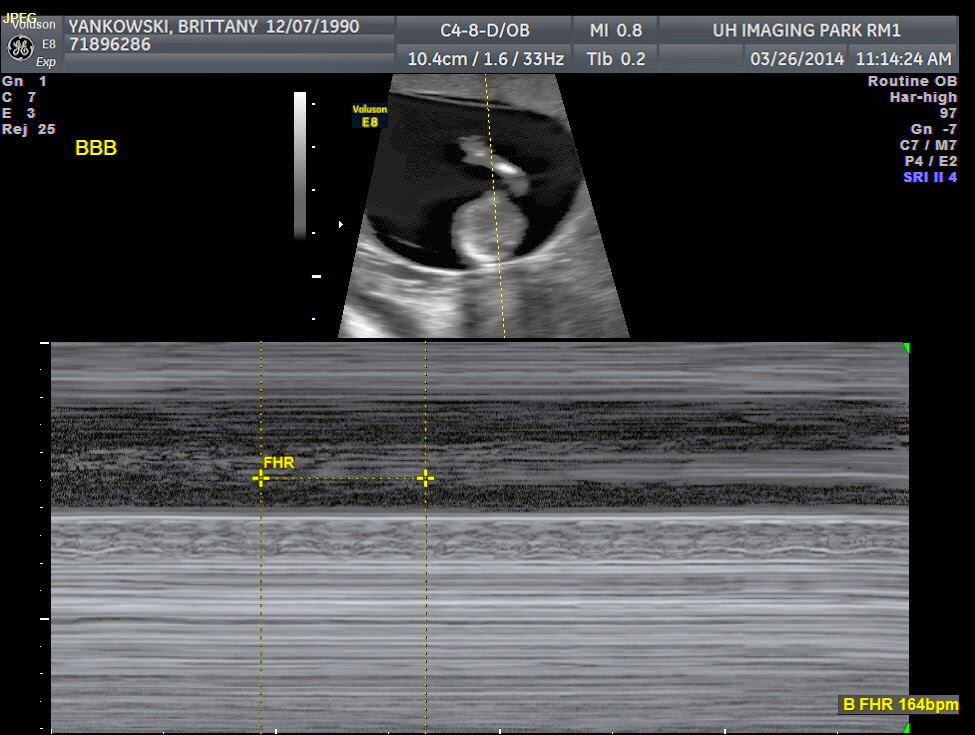

Baby B ^

So, all the babies had great heartbeats...

They were all wiggly and look pretty healthy overall.

However, Baby B had a think NT, which could be an indication of Downs Syndrome. This is not a reliable factor, but the doctor said it measured on the "higher end of high" and suggested genetic counseling to consider an amniocentesis or CVS testing for a more clear picture. Despite the fact I do not have many of the other risk factors, triplets carry a higher risk than singletons.

This also could point to potential heart problems, so Baby B will get a fetal echo around 18 weeks to make sure everything looks good on that end.